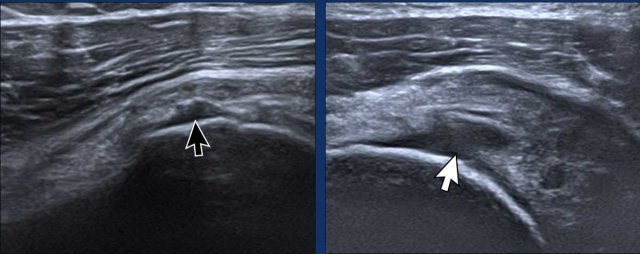

Image during exoratation (left) and endorotation (right) Image during exoratation (left) and endorotation (right)

Impingement

During endorotation a normal subscapular tendon should show almost complete passage underneath the coracoid process.

Impingement is suspected when a residual portion of the tendon is still visible during maximum endorotation.

Images

During endorotation there is incomplete passage under the coracoid and buckling of the subscapular tendon.